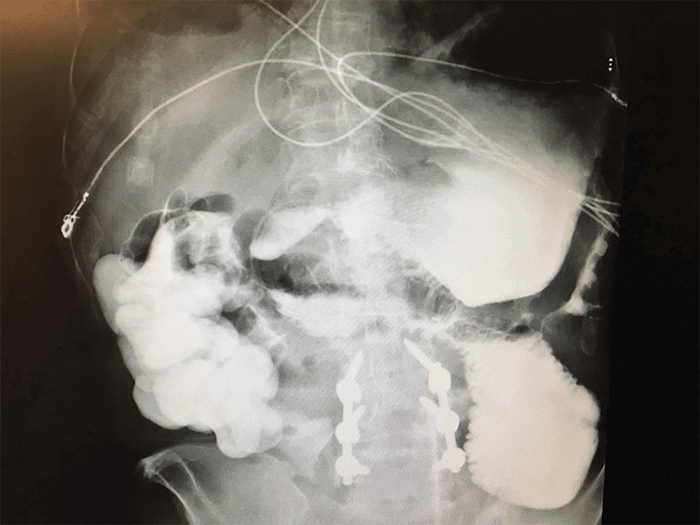

A 72-year-old male presented with one year of weight loss, diarrhea, and malnutrition after a simple gastric-small bowel side-to-side anastomosis without resection for an obstructing pyloric ulcer. His additional history included coronary artery disease with stent placement, oropharyngeal dysphagia secondary to a vocal cord injury from prior intubation, chronic back pain on narcotics, and lumbar fusion. During the year after the index operation, he sought advice at multiple academic medical centers in the United States for investigation without a satisfying diagnosis. Examination revealed a cachectic, emaciated, Caucasian male with a soft scaphoid abdomen with a well-healed midline scar. Initial imaging included an upper gastrointestinal contrast study with small bowel follow-through, revealing a patent anastomosis and contrast entering the colon within fifteen minutes (Figure 1).

Figure 1. Upper Gastrointestinal Contrast Study with Small Bowel Follow-Through. Published with Permission

A) Upper gastrointestinal contrast study with small bowel follow-through examination demonstrating no evidence for obstruction at the site of anastomosis; contrast had already reached colon within 15 minutes; B) at sixty minutes, nearly all contrast is present in colon—note: normal gastric emptying function preoperatively